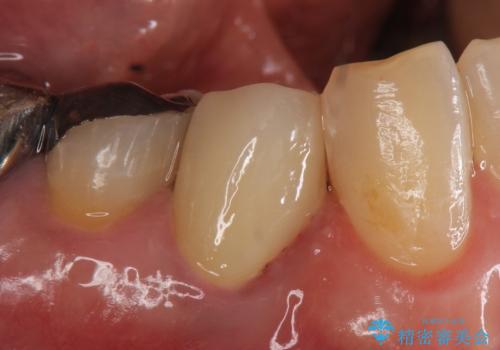

再根管治療終了後、オールセラミッククラウンによる補綴を行いました。

今回用いたオールセラミッククラウンは、ジルコニアフレームという白い素材の上にセラミックを盛っているため審美性が非常に高いのが特徴です。

またジルコニアは人工ダイヤモンドの材料にも使われているほど高い強度を持っており、そのためオールセラミッククラウンは審美性だけでなく、奥歯やブリッジの補綴も可能とするクラウンです。